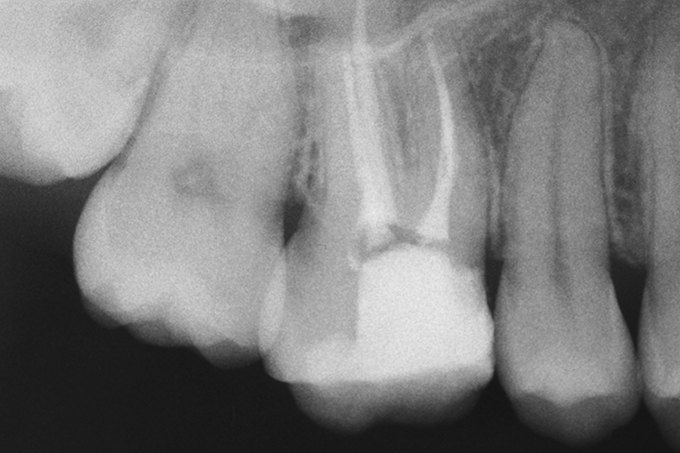

Initial situation: The patient was complaining about the lack of a contact point to the neighboring tooth. She was suffering occasional pain while chewing.

The image shows an insufficient RCT.